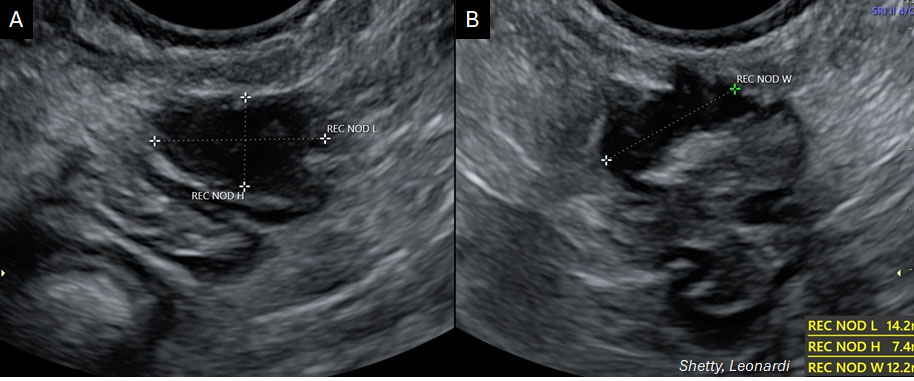

When assessing the bowel, hypoechoic nodules may be found in the upper (intraperitoneal) and lower (retroperitoneal) rectum (Figure 5). Since the lower rectum is outside the peritoneal cavity, and thus not accessible during laparoscopy, detection of nodules in this area can be valuable for preoperative planning. On the other hand, it is extremely rare for lesions to affect exclusively the retroperitoneal rectum or rectovaginal septum. In the case of severe endometriosis and POD obliteration, anatomical planes can be distorted, giving the impression that the nodules are retroperitoneal when in fact, they were formally intraperitoneal and have simply become invisible (i.e. beneath the surface) laparoscopically due to severe adhesions. The "sliding sign" to evaluate POD obliteration can be elicited with one hand holding the probe and the other on the patient’s lower abdomen. A "positive sign" is characterized by the rectum sliding against the uterus (Video 2), whereas movement of the rectum and uterus in unison ("negative sign") suggests POD obliteration (Video 3).

.jpg?1645203)

5

Transvaginal ultrasound images (sagittal (A) and transverse (B) views) showing a hypoechoic nodule (calipers) infiltrating the anterior rectal wall, consistent with bowel endometriosis.